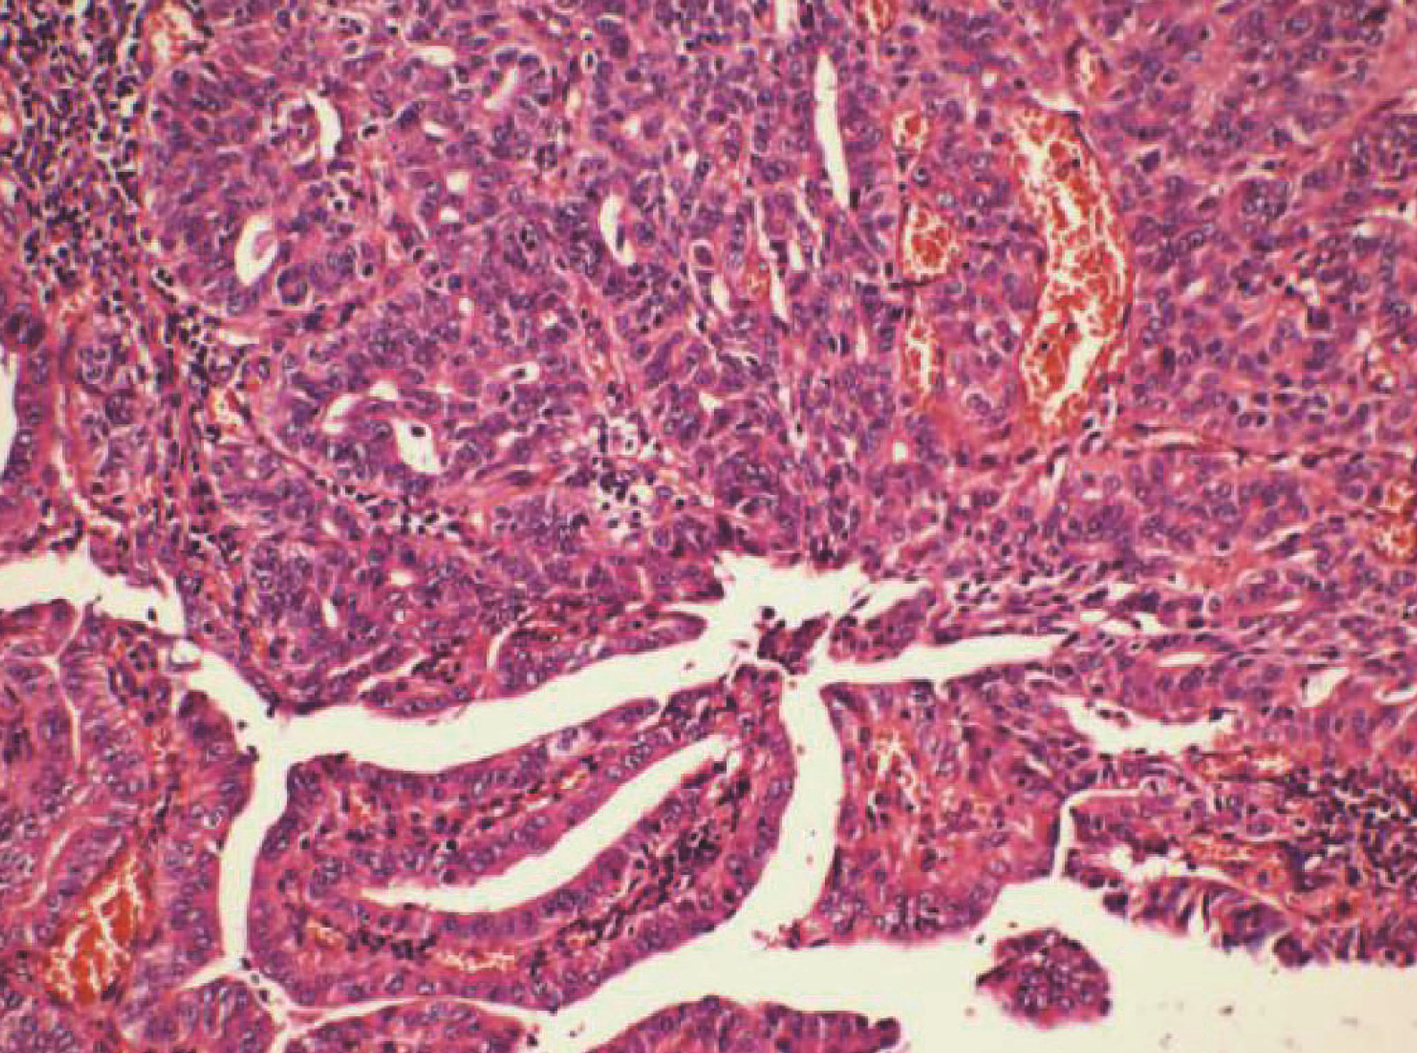

肝组织病理学诊断肝肺吸虫病1例报告

刘洋, 李朝霞, 武彤, 时佳鹤, 于鸽, 辛桂杰

2022, 38(5): 1116-1118. DOI: 10.3969/j.issn.1001-5256.2022.05.027

摘要(926) HTML (473) PDF (2302KB)(74)

摘要: